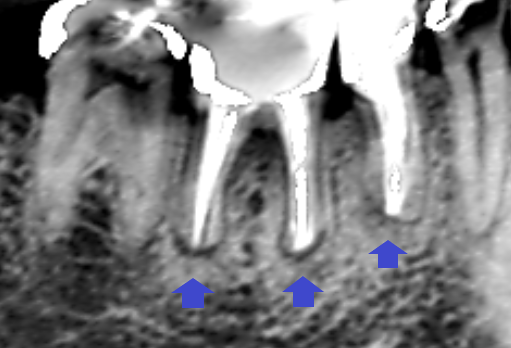

6カ月後の経過観察時のCT画像です。下顎第二小臼歯と第一大臼歯の根の先にあった膿の影が消え、歯槽骨が再生しています。

精密根管治療により、下顎第二小臼歯と第一大臼歯の全ての膿が改善し、ブリッジとインプラントを回避することができました。根管充填は、その人の歯の運命を決めてしまう重要な治療です。当医院は保存治療専門の歯科医院です。本ケースのように歯を残し、長持ちさせる治療に力を入れています。